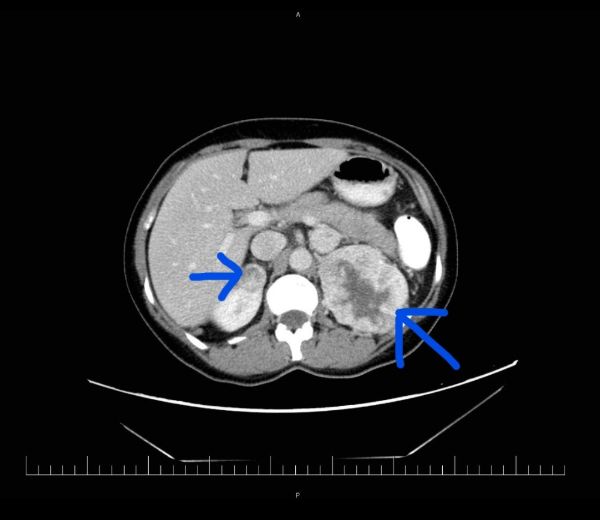

Muž 45 let – potíže s mikcí

Jste lékař urolog a přichází k vám pacient odeslán od praktického lékaře (PL). PL k Vám odesílá muže ve věku 45 let, pro nespecifické mikční potíže, které se objevily po prochlazení. Krev v moči pacient nepozoroval, lékařem to však nebylo došetřeno. Pacient nebyl doposud urologicky sledován, neléčil se.